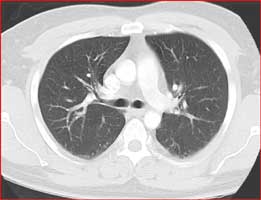

If your physician suspects more advanced involvement of the respiratory system, advanced imaging modality, such as CT or MRI, can be further utilized. CT scan of the chest is particularly helpful in evaluating for infectious etiology, lung cancer, pulmonary embolus, chronic lung disease or pleural pathology.

Normal Chest CT Scan